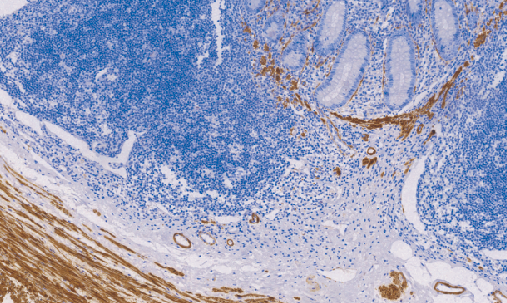

Calponin是结合肌球蛋白和F-肌动蛋白的一种钙调蛋白,与平滑肌细胞收缩和调节有关。为平滑肌特异性蛋白,表达于平滑肌及肌上皮细胞胞质。用于标记乳腺肌上皮及平滑肌细胞肿瘤。肌纤维母细胞也可阳性。

- 阳性部位:胞质

- 适用组织:石蜡切片

- 预处理:热修复